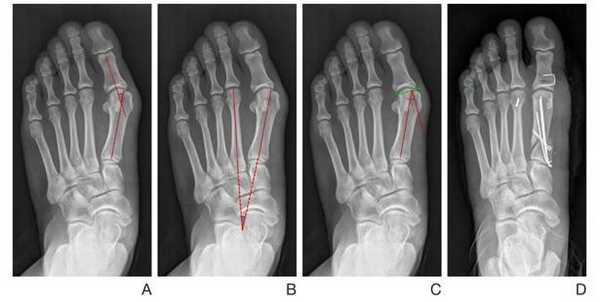

При планировании оперативного пособия выполняются рентгенограммы в прямой и боковой проекции. Производится расчёт углов вальгусного отклонения 1 пальца, угол между 1 и 2 плюсневыми костями, угол артикуляции 1 плюсневой кости. Исходя из рассчитанных углов, выбирается оптимальный метод остеотомии для коррекции имеющейся деформации.

Хирургическая тактика обсуждается с пациентом. Разъясняются особенности хирургического доступа, анестезиологического пособия, последующей реабилитации. Эту пациентку беспокоила деформация только 1 луча, вмешательства на 2-3-4-5 лучах стопы не потребовались.

SCARF

Z-образная остеотомия Scarf - это золотой стандарт лечения вальгусной деформации. Она позволяет установить головку плюсневой кости под нужным углом. В ходе хирургического вмешательства врачи также убирают деформацию суставной капсулы и меняют направление некоторых сухожилий.

Когда операции Scarf недостаточно - хирурги делают проксимальную клиновидную остеотомию или артродез.